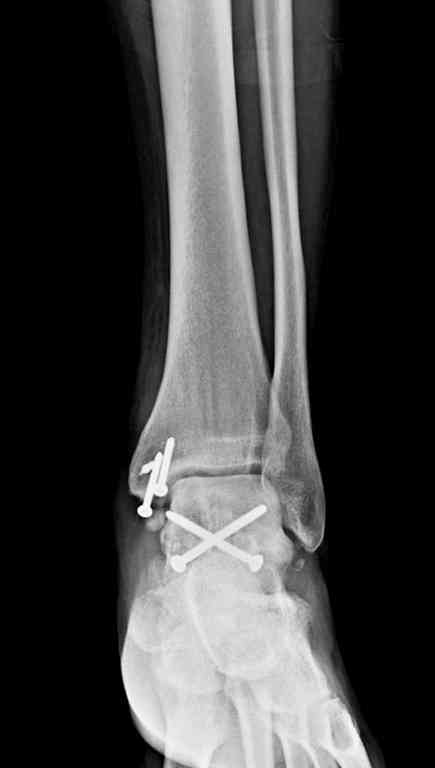

Здесь на фото примеры:

Переломовывих тарана с повреждением медиальной стороны. Через 4 часа после поступления проведена репозиция и фиксация тарана после Irrigation&Debridment. Частичное несращение медиальной лодыжки не беспокоит, вернулся к активному образу жизни. Полная нагрузка разрешена через 11 недель. Финальные снимки через 11 месяцев.